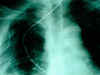

Esophageal perforation is a serious condition with a high mortality rate. Successful therapy depends on the size of the rupture; the time elapsed between rupture and diagnosis, and the underlying health of the patient. Common causes of esophageal perforation include medical instrumentation, foreign-body ingestion, and trauma. A case of esophageal perforation due to fish bone ingestion in a 67-year-old male is described here, with a review of the pertinent literature. The patient presented with chest pain, fever and right-sided pleural effusion. Initial evaluation was nondiagnostic. The water-soluble contrast swallow test showed no evidence of leakage. Computed tomography scan demonstrated a pneumomediastinum, and right-sided hydropneumothorax. The patient was successfully treated using conservative measures.